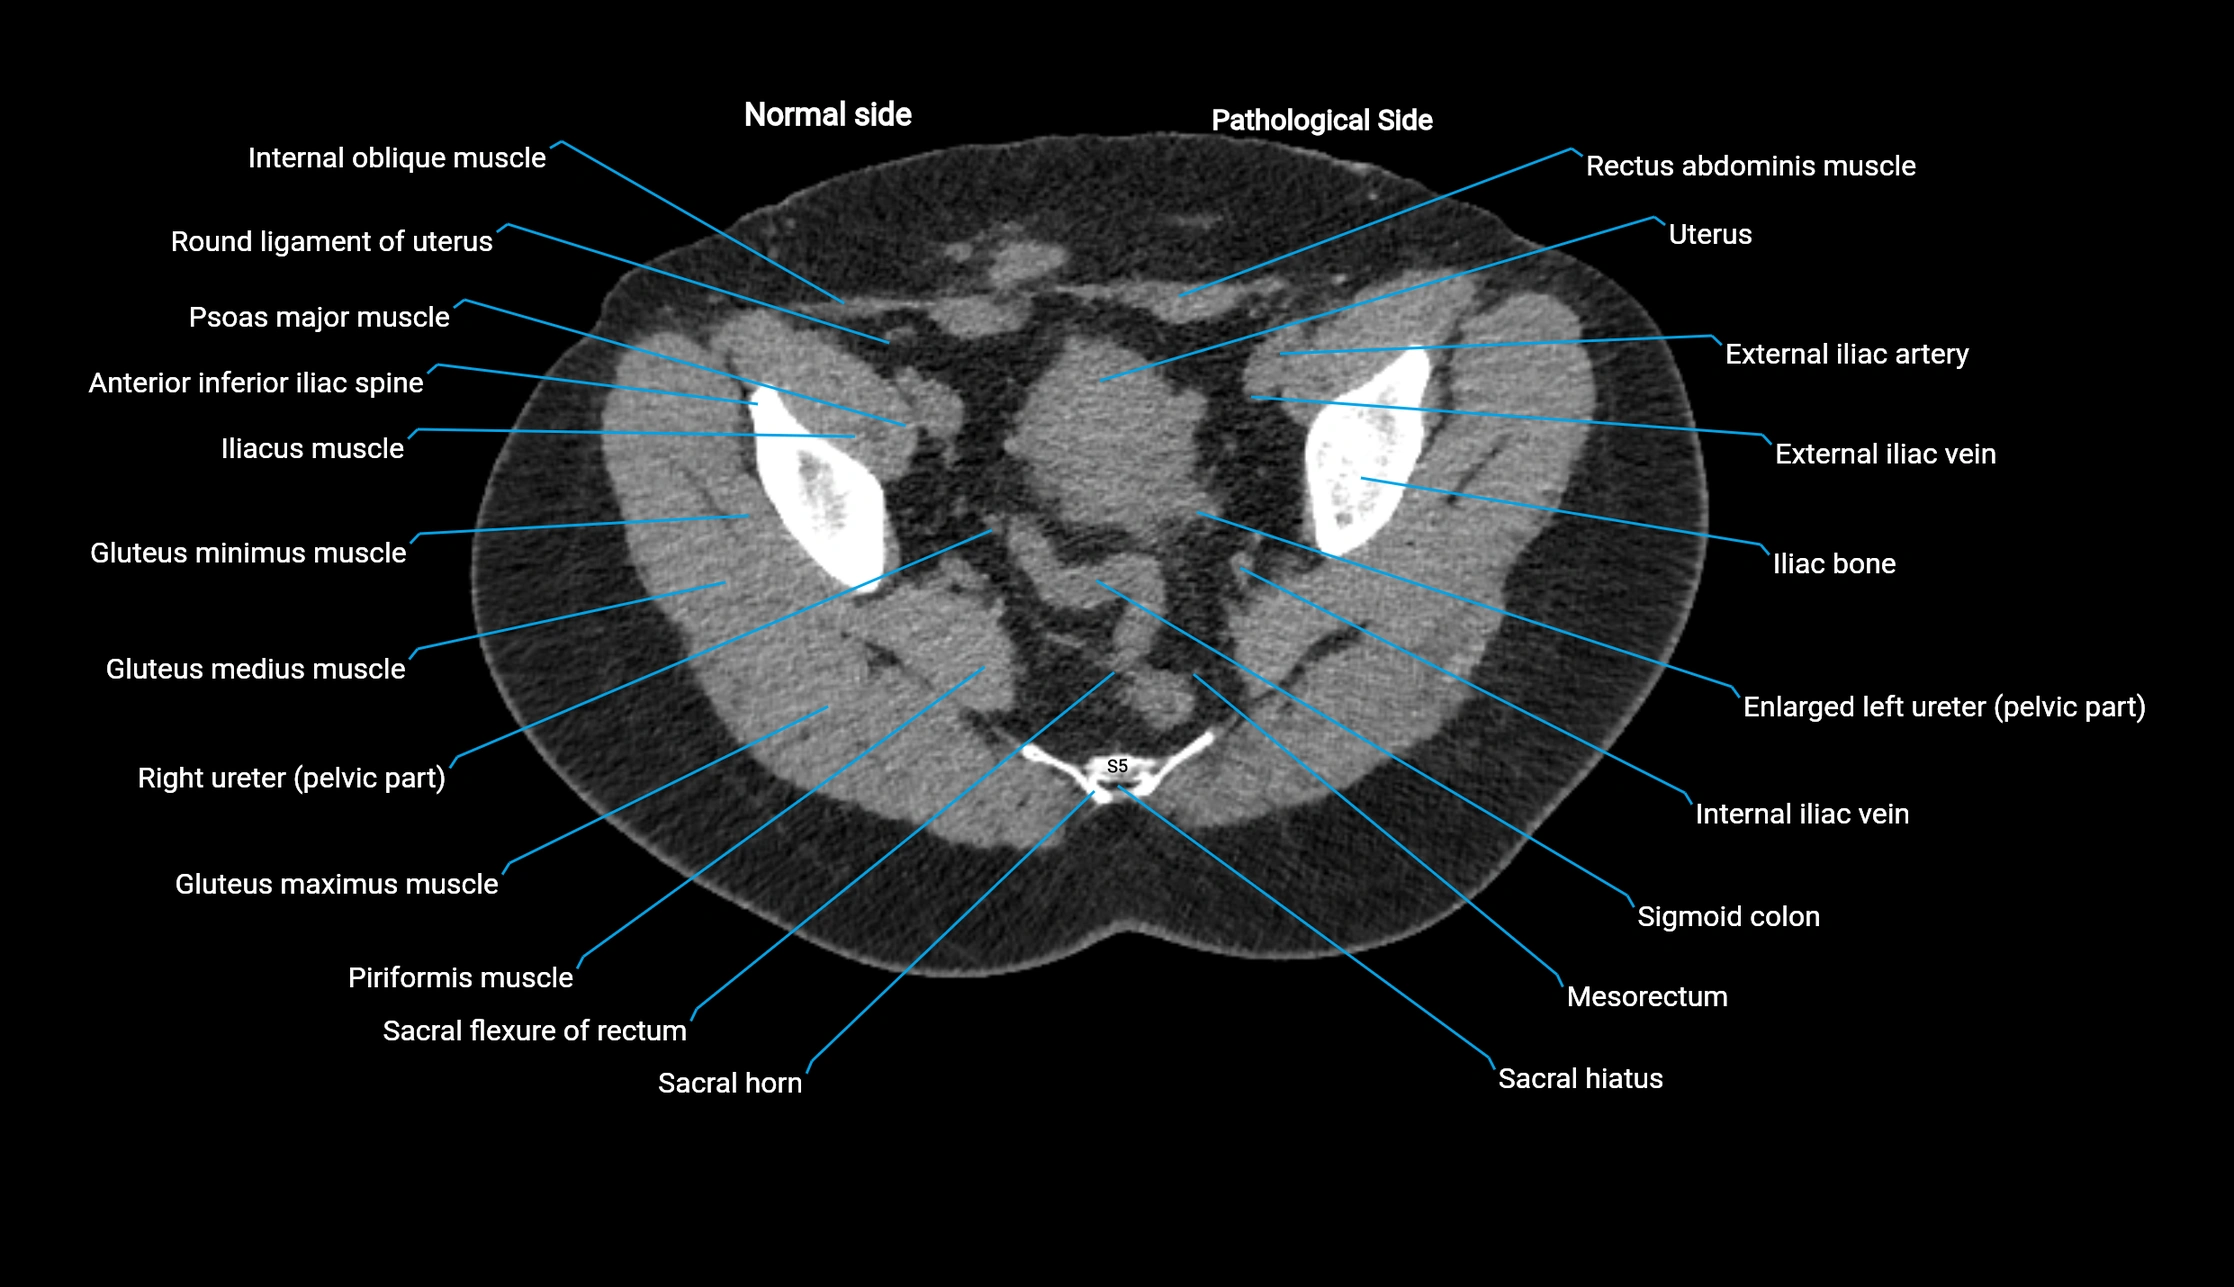

MRI image

image